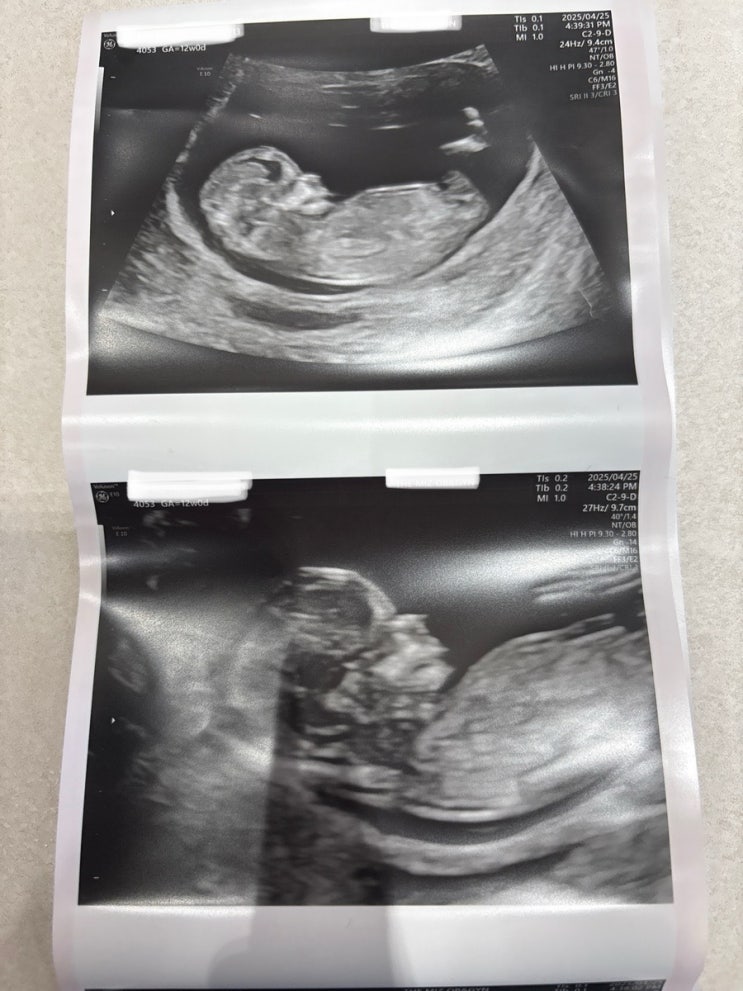

12주 1차기형아검사 장꾸맘 각도법 12주 정확도 성별맞추기 후기

임신 12주가 되어서 성별이 엄청 궁금했었다 ! 그 전부터 많이 들어서 알고있었던 장꾸맘에게 물어보기로 ...